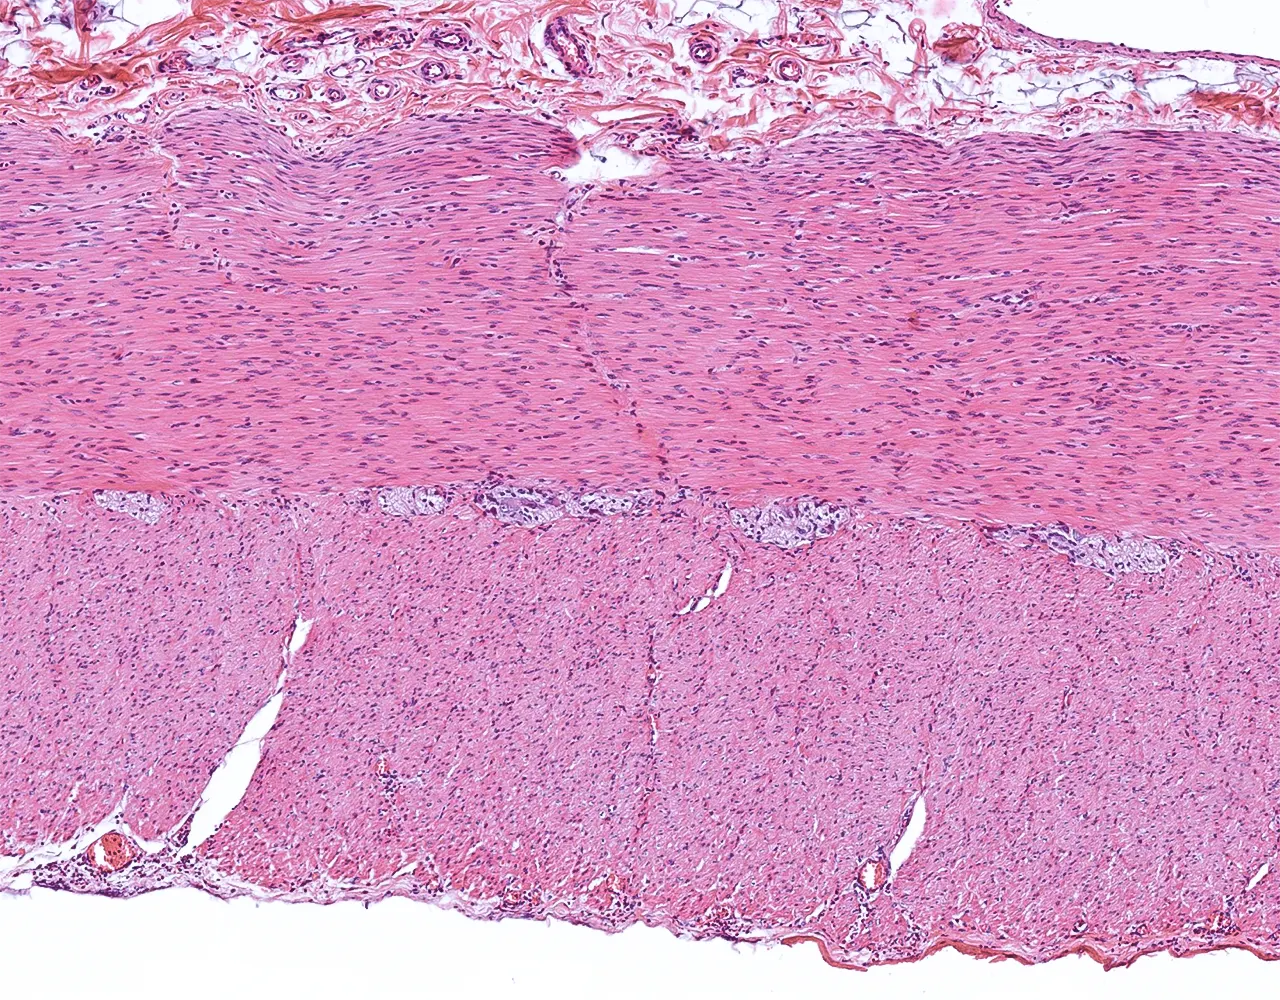

- Le gros intestin comprend le caecum, le côlon, le rectum et le canal anal.

- Le côlon ascendant et le côlon descendant sont majoritairement rétropéritonéaux, alors que le côlon transverse et le côlon sigmoïde sont intrapéritonéaux et recouverts par la séreuse.

- Le rectum est partiellement recouvert par une séreuse dans sa portion proximale, le reste du rectum est entouré par une adventice.